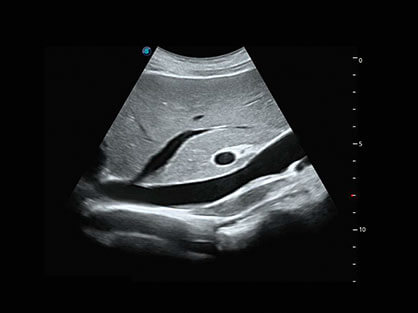

结合银河集团官网超宽频带探头技术优势,能够更好地获得高分辨力与高穿透力的平衡,保证图像质量,为临床诊断保驾护航。

微米成像技术提升了对组织斑点噪声信号的抑制能力,并进一步强化边界信息,从而获得清晰图像。